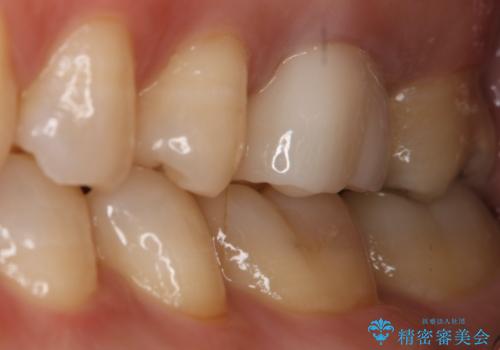

銀歯を白くしたい セラミックインレー

- 左上7番の銀歯をセラミックにやり変え希望の患者様です。

切削量・形態からセラミックインレーでの治療を計画しました。

銀歯とその直下のう蝕を除去した後、CRにて裏層しています。

インレー装着の際はラバーダムを使用しています。